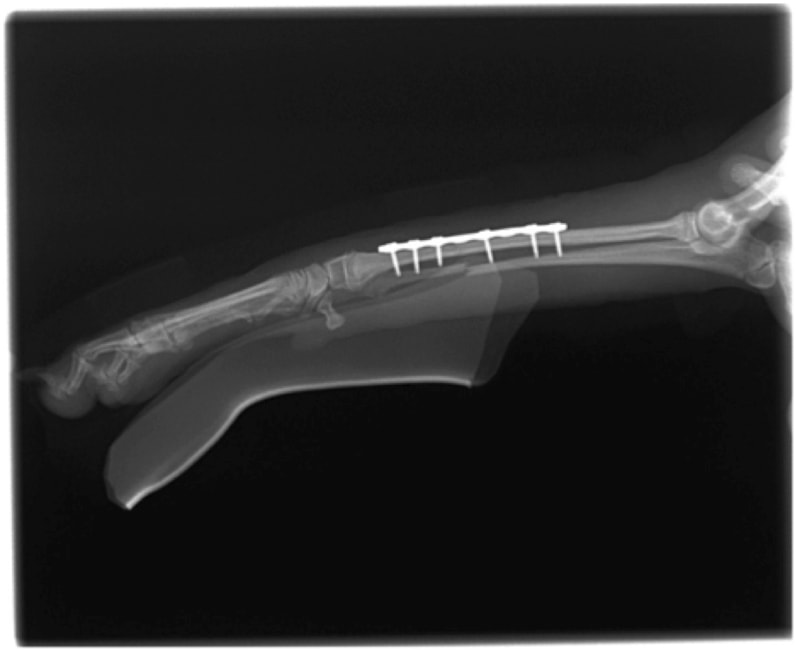

症例:交通事故による椎体脱臼

柴犬:9歳、避妊雌

交通事故直後、胸腰部に激しい疼痛、両後肢に完全麻痺を認め、シェフシェリントン徴候を呈していました。レントゲン検査において、第11-12胸椎間の脱臼が認められました。

脊髄の減圧、脊柱管の再構築・安定化を目的に、片側椎弓切除術およびMatrixMANDIBLE Plateによる椎体固定を実施しました。

隣接椎体を架橋するようにプレートを設置しました。

術後レントゲン写真